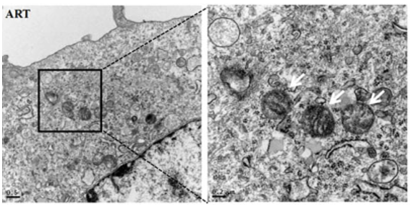

形态学特征:超微结构显示,铁死亡时细胞膜断裂和出泡,线粒体萎缩、线粒体脊减少甚至消失、膜密度增加、细胞核形态正常,但缺乏染色质凝集;电镜下观察到胞内线粒体变小、膜密度增高。

透射电镜直接观察细胞形态;